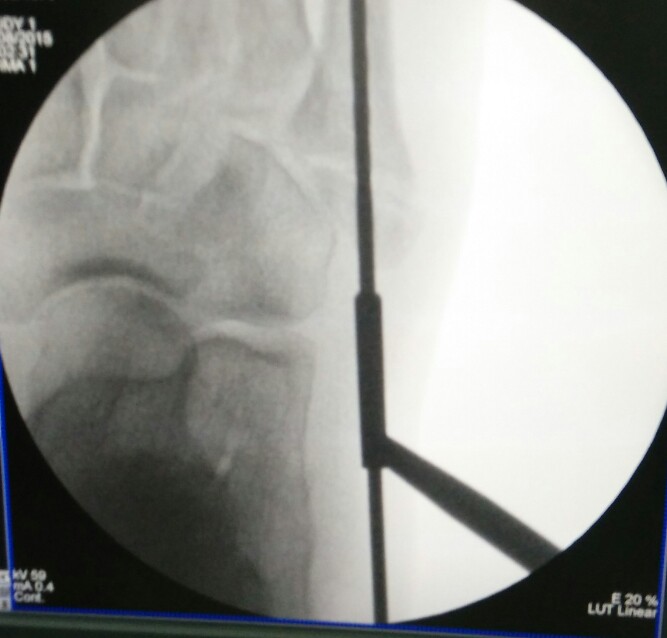

Percutaneous cannulated screw fixation of this displaced avulsion fracture of the 5th metatarsal base was performed.

This procedure is done via a small incision and guided by x-rays fluroscopy.